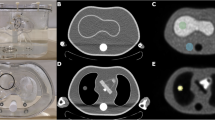

The large differences in image blur due to the positron flight in human compact bone, soft tissue and lung tissue from some characteristic positron point sources are illustrated in Fig. 1. The corresponding one-dimensional annihilation probability distribution functions \( {aPSF({}_{z}X^{A} ,T_{i} ,x)} \), as a function of distance from the point source, are presented in Fig. 2 for each radionuclide and for each of the selected tissues. All projected distributions of annihilation events were cusp shaped around the positron point source. Due to this characteristic shape, all related FWHM values were well within the system resolution of a modern PET camera (4–5 mm). The corresponding \( {FWTM(T_{{j,}} {}_{Z}X^{A} )_{{aPSF}} } \) values, on the other hand, varied from 0.65 mm in bone up to 2.7 mm in lung tissue for 18F and from 4.5 mm in bone up to 20.3 mm in lung tissue for 82Rb. This is illustrated in Table 1 together with the values at the 20% level, \( {FW20M(T_{{j,}} {}_{Z}X^{A} )_{{aPSF}} } \).

The impact of the positron flight on spatial resolution in PET imaging has often been considered but has generally not been recognised as a major limiting factor for PET spatial resolution. A drawback of most of these investigations is that they have been restricted to positron transport in water. However, the present work revealed large differences in the slowing down of positrons before annihilation for various human tissues. These findings may be of clinical importance, especially in imaging of tumours sited within or at the border of the lungs. In lung tissue, the positron contribution to image blur was found to be up to three times larger than in soft or adipose tissue and five times larger than in bone tissue. Even though tumour masses in the lungs may have a density similar to soft tissue, positrons emitted close to their surface will act to blur the tumour edge and impair their detectability.